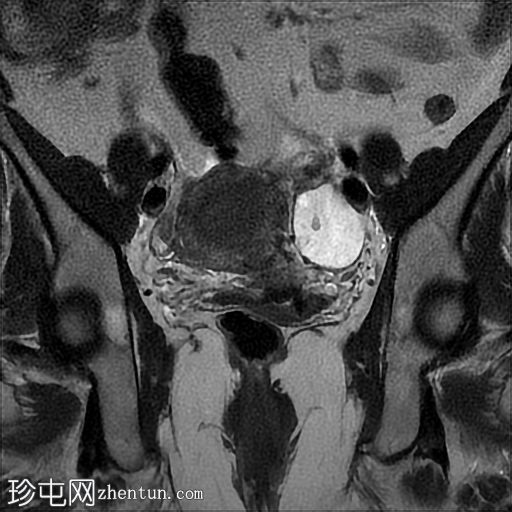

冠状位

T2加权像

3.jpg

左侧卵巢增大,呈弥漫性低T1信号和高T2信号,可见周边卵泡,部分卵泡除周边卵泡周围有环状强化外,无明显实质强化。左侧附件蒂呈漩涡状,提示卵巢扭转。

巨大卵巢水肿是一种罕见疾病,几乎总是单侧发生,且多见于右侧。复发性卵巢部分扭转是其发病机制的主要怀疑因素,可导致静脉和淋巴回流受阻,进而引起卵巢间质肿胀和水肿。

本病例展示了这种罕见疾病在左侧发生的罕见表现。